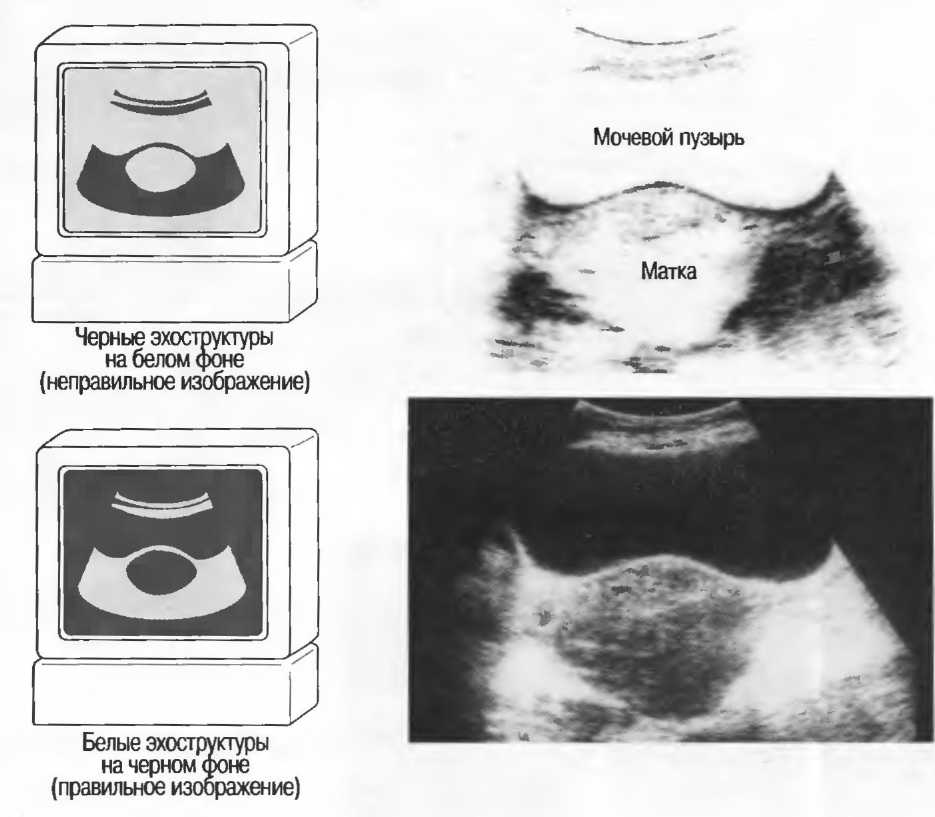

Фон получаемого изображения

Получаемое изображение на экране может быть преимущественно черным или преимущественно белым. Оно может иметь белый фон с черными отраженными сигналами (рис. 9, верх) или черный фон с белыми отраженными сигналами, определяемыми в виде точек или линейных структур (рис. 9, низ). Обычно есть кнопка, позволяющая менять фон; если нет — инженер должен настроить аппарат таким образом, чтобы всегда был черный фон с бельшиогпраженньшисигналал1и(рис. 9, низ).

Рис.9. Поперечные срезы увеличенной матки на различном фоне.